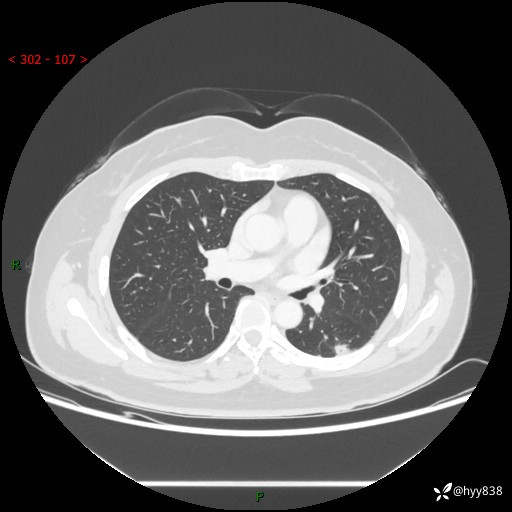

胸部CT平扫(2023.3)